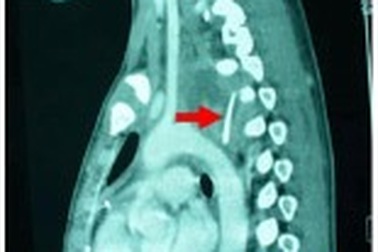

Xương gà xuyên thủng thực quản, bệnh nhân suýt tử vongNhập viện trong tình trạng sốt cao, đau tức ngực, ho khạc ra máu,… qua chẩn đoán hình ảnh, bác sĩ ghi nhận bệnh nhân bị hóc xương gà gây thủng thực quản. Không thể gắp xương bằng nội soi, bác sĩ buộc phải mổ cấp cứu lấy mảnh xương dài 3cm cứu bệnh nhân.

Suýt tử vong vì xương gà đâm thủng thực quản, phế quảnNhập viện trong tình trạng sốt cao, đau ngực, khó thở… qua chẩn đoán hình ảnh, bác sĩ ghi nhận bệnh nhân bị hóc xương gà gây thủng thực quản, phế quản. Không thể gắp xương bằng nội soi, bác sĩ buộc phải mổ cấp cứu lấy mảnh xương dài 3cm cứu bệnh nhân.